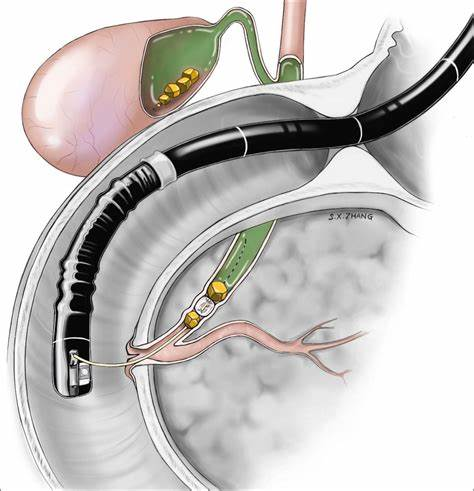

1. 내시경적 역행성 담췌관조영술(ERCP)

- 총담관 담석은 심각한 합병증을 동반할 수 있으므로 증상이 없는 총담관 담석이라도 제거를 해야 한다.

- 담석 혹은 담도염의 증거가 있는 경우에 시행한다. 뚜렷한 증거 없이 진단적 목적으로 시행하지 않는다.